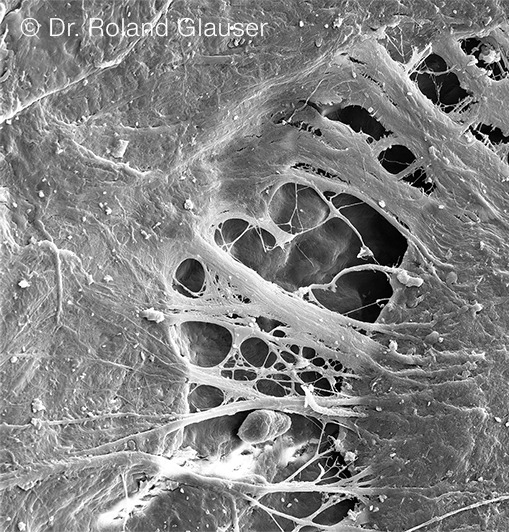

Mit Symbionic Teeth ist dies erstmals möglich. Symbionic Teeth erzeugen eine mukosale Schutzbarriere nach Vorbild des natürlichen Zahns. Voraussetzung für das Entstehen einer mukosalen Schutzbarriere ist das Verwachsen von oralem Weichgewebe mit dem Halsbereich eines Symbionic Tooth. Dieser Vorgang konnte bei Symbionic Teeth der Marke Patent™ erstmals überhaupt für eine Zahnersatzlösung nachgewiesen werden (Abb. 1).3-5 Damit stellen Symbionic Teeth die konsequente Weiterentwicklung von Zahnimplantaten dar.

Die mukosale Schutzbarriere schirmt das Gewebe vor Plaquemigration und Krankheitserregern wie Bakterien ab (Abb. 2). Dadurch können Zahnersatzspezialisten die Gewebegesundheit bei ihren Patienten erhalten und die für Zahnimplantate typischen Nebenwirkungen (43% Mukositis und 22% Periimplantitis; Abb. 36) deutlich reduzieren respektive gänzlich vermeiden.1, 2 Dies ermöglicht langfristig stabile ästhetische Resultate.1

- Mukosale Schutzbarriere verhindert Plaquemigration entlang des Patent™ Halsbereichs tief in die Gewebe (Abb. 2).3-4